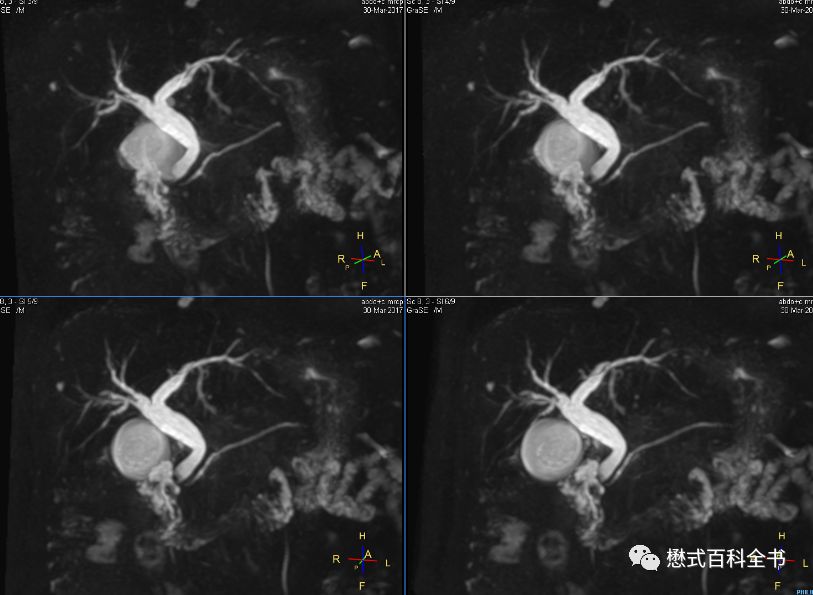

图27:胰头区囊性占位,肝内胆管、胰管扩张(Ingenia 1.5T图像)

有的时候,如果要诊断胆囊结石或者胆管结石,相对难度不大。明显的结石,经常在常规的横轴位T2WI或者冠状位T2WI上即可显示。难度大的在于胆总管下段的占位或者不确定的梗阻。